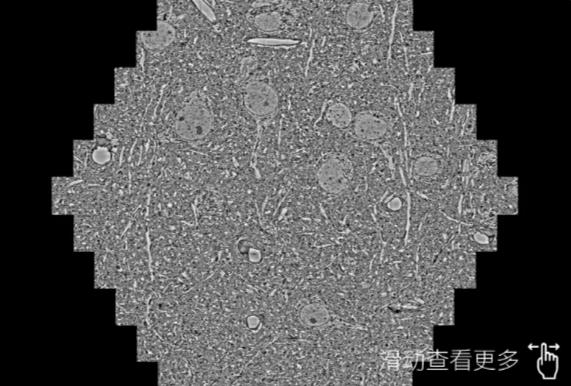

鼠脑切片。左图使用舒兰蔡司舒兰扫描电镜MultiSEM706对165μmx143pm面积区域成像,耗时仅需1.5秒。右图为鼠脑切片中30μm区域放大效果。样品由芝加哥大学B.Kasthuri提供。